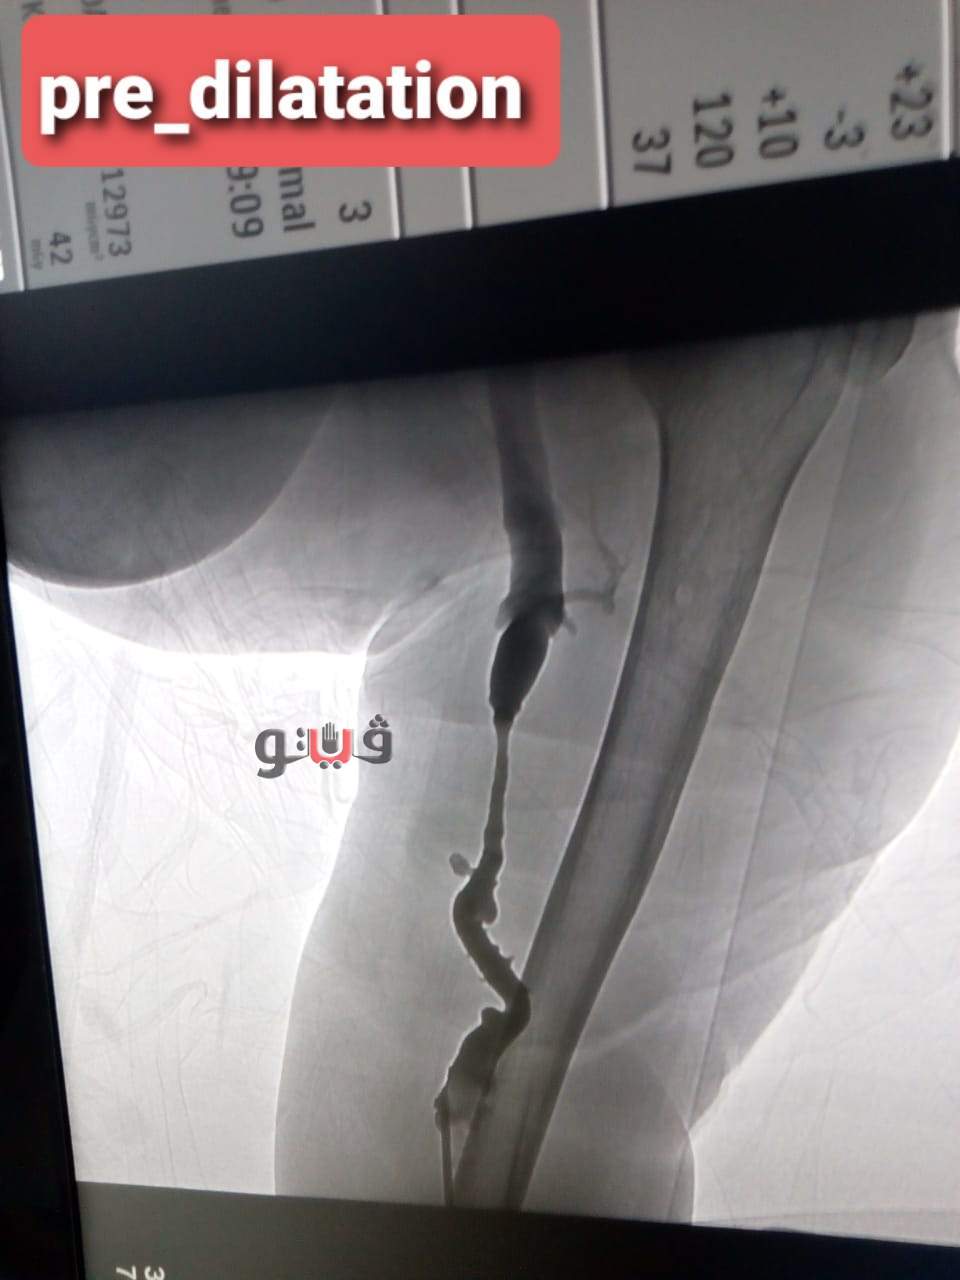

أعلن اليوم الدكتور سعد مكى وكيل وزارة الصحة بالدقهلية عن قيام فريق طبى بمستشفى المنصورة العام الجديد (الدولي) ،بإنهاء معاناة مريضة فشل كلوى تبلغ من العمر 57 عاما كانت تعاني من ضيق شديد بالوصلة الوريدية الشريانية (وصلة الغسيل الكلوى) بالذراع الأيسر.

وتمكن الفريق الطبي من استقبال المريضة وعمل قسطرة تشخيصية وتصوير اوردة الذراع الايسر كما تم عمل تدخل علاجي بالقسطرة عن طريق توسيع الوصلة باستخدام البالونات عالية الضغط حيث تم توسيع الوصلة بنجاح .